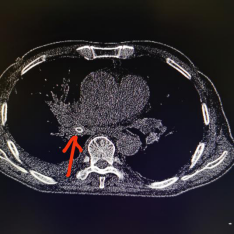

之后,李老伯持续发热不退,直到出现比较重的胸闷症状,再次到医院就诊,做了胸部CT后,医生发现,李老伯右肺中间支气管被一颗大约1cm*1cm大小的杨梅核堵住了(人体右肺中间支气管直径也就1厘米-1.2厘米,杨梅核相当于完全卡在了支气管内),并且出现了大片的阻塞性肺炎和炎性胸腔积液。这时,距离李老伯吞下这颗杨梅核,已经过去了16天。

邵逸夫医院胸部CT 医院供图